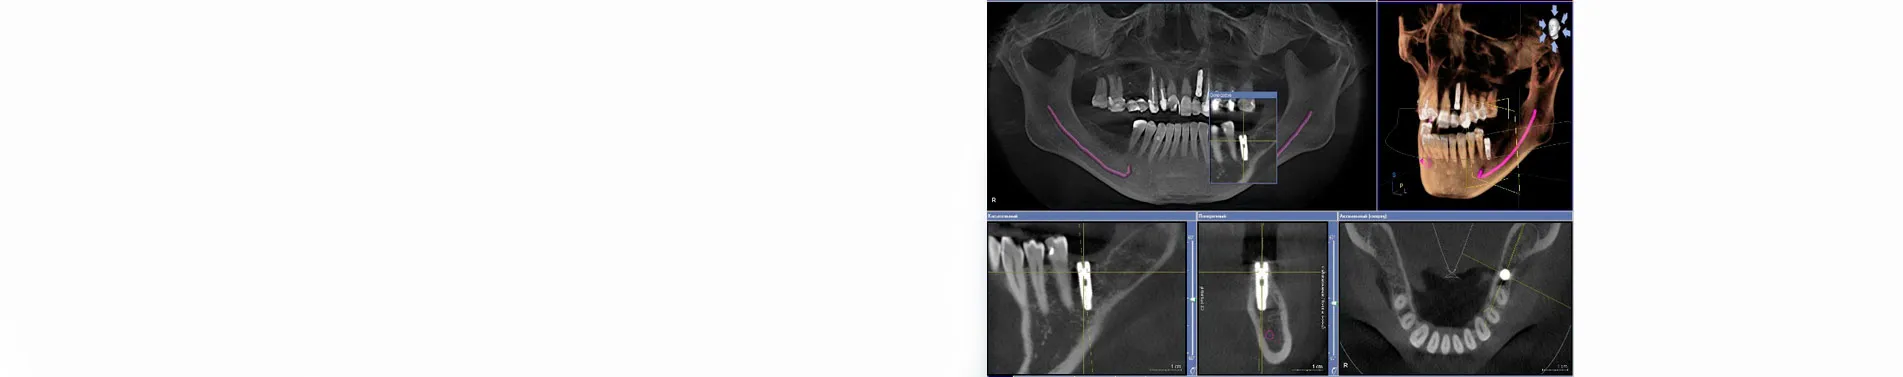

- зробити рентгенографічне 3D дослідження для визначення розміру і місцеположення імпланта.